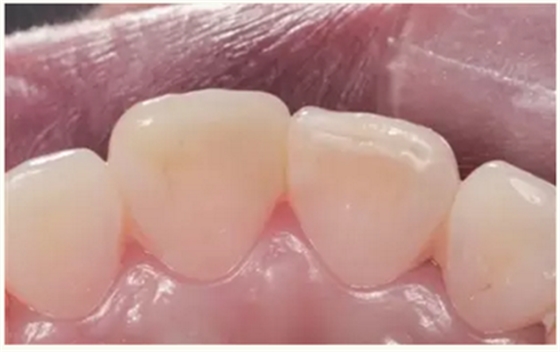

牙体树脂美学修复适用于对牙体修复效果有美学要求的前牙或者后牙。对于患者而言,前牙修复效果更为直观。因此,临床上对于前牙美学修复的需求更为迫切,常见的修复类型为及切角的前牙牙体缺损。治疗的过程一般为①比色、②缺损牙体的树脂预修复(直接修复)或者取模翻制石膏模型的基础上制作蜡型恢复缺损牙体(间接修复),③硅橡胶制作舌侧导板,④上橡皮障,牙体预备(洞缘斜面),⑤酸蚀、粘结,⑥树脂分层充填,⑦修形、抛光,⑧完成。

▲术后一月(唇侧)

▲术后一月(舌侧)